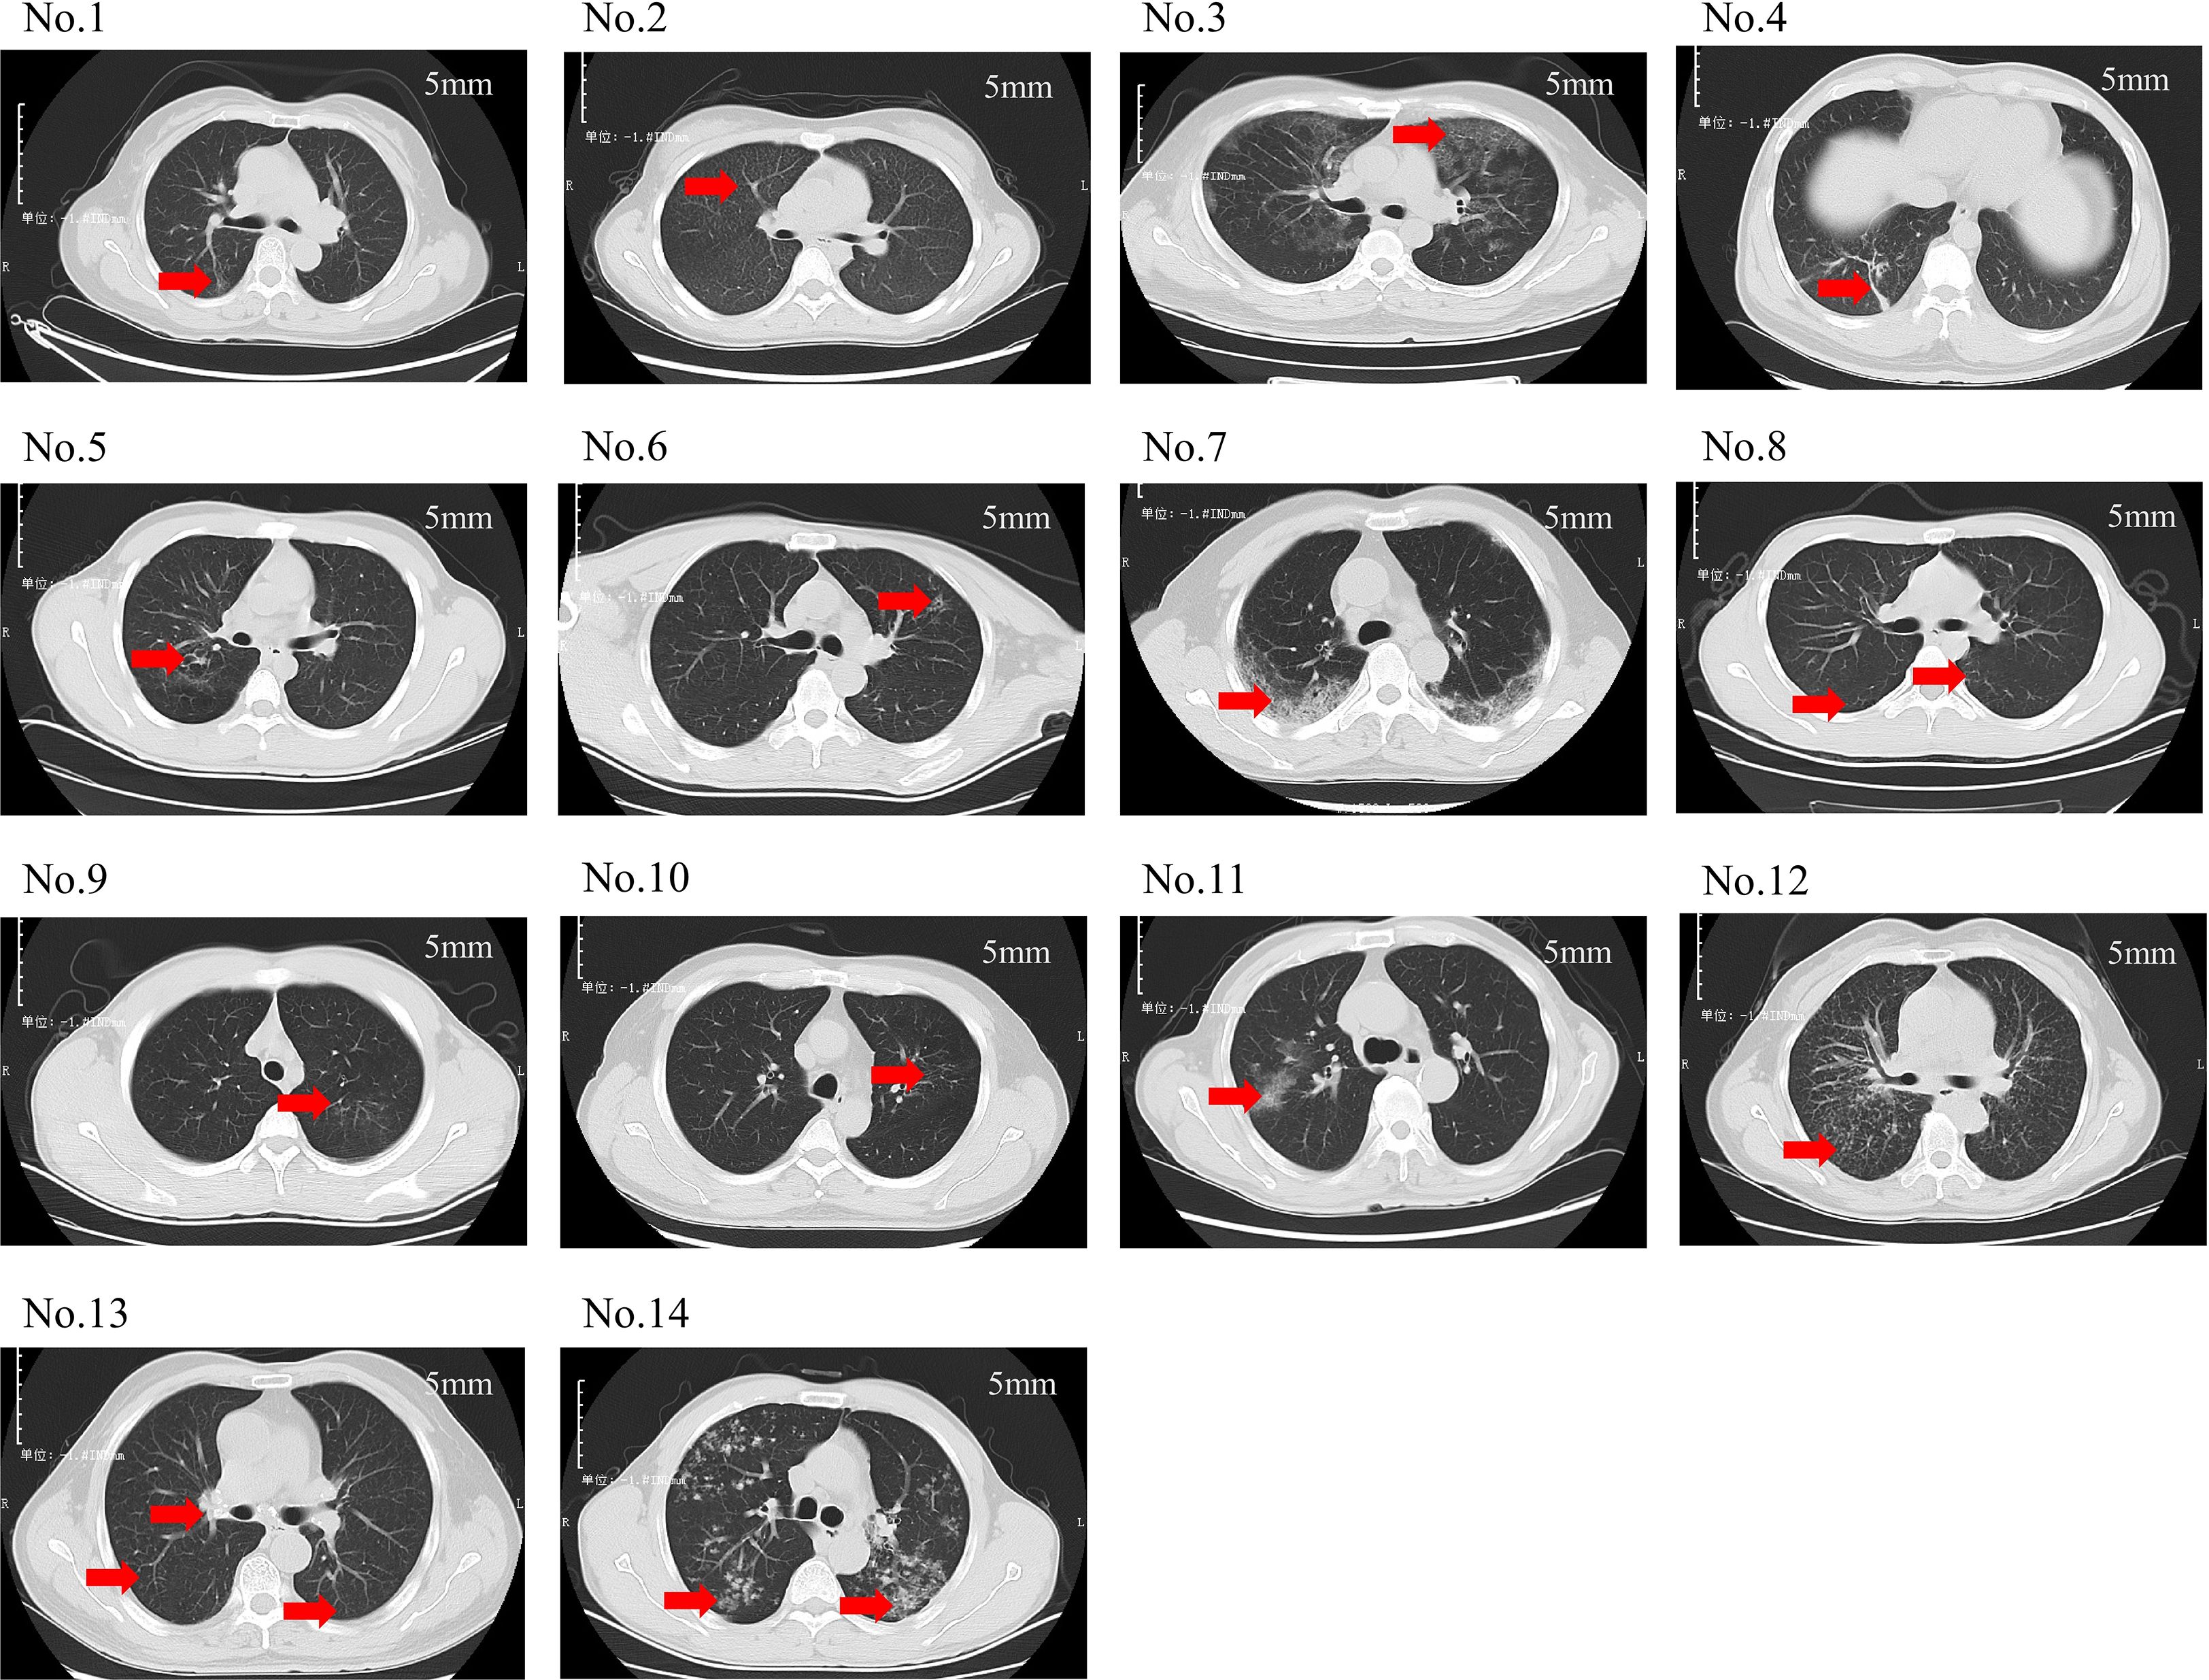

Figure 2 depicts the pulmonary imaging manifestations of 14 positive patients. A further comparative analysis on the imaging features of patients was carried out in the low-sequence group and the high-sequence group (Table 3). As our investigation findings illustrated, a total of 13 patients exhibited patchy shadows. Additionally, the occurrence rates in the low-sequence group and the high-sequence group were 100.00% and 87.50%, respectively. Cord-like shadows were observed in 11 patients, and the occurrence rates in these two groups were 83.33% and 75.00%, respectively. Bronchiectasis occurred in 5 patients, and the occurrence rates in these two groups were 33.33% and 37.50%, respectively. Nodules occurred in 7 patients, and the occurrence rates in both groups were 50.00%. Cavitation was merely observed in 1 patient, exclusively in the high-sequence group. Ground-glass opacities were present in 2 patients, both belonging to the low-sequence group. Rare manifestations included pericardial effusion and enlargement of mediastinal and hilar lymph nodes. No statistically significant differences were noted in the distribution of these imaging features between the two patient groups.

Figure 2

CT scan images of lungs labeled No.1 to No.14, each marked with a red arrow indicating areas of interest. The scans display variations in lung tissue density and patterns, each captured at a slice thickness of 5 mm.

Figure 2. Chest CT scans of 14 patients. (No.1: Linear opacities are observed in the posterior segment of the right upper lobe. No.2: Diffuse miliary nodules are distributed throughout both lungs. No.3: Ground-glass opacities are noted in all lobes of both lungs. No.4: Scattered patchy and nodular shadows are observed in the posterior basal segment of the right lower lobe. No.5: Bronchiectasis is identified in the posterior segment of the right upper lobe. No.6: A small cavity is formed in the left upper lobe. No.7: Spotty, patchy, and linear shadows are seen near the pleura in both lungs. No.8: Small nodular shadows are observed in the dorsal segment of both lower lobes. No.9: Minor ground-glass opacities are noted in the apical posterior segment of the left upper lobe. No.10: Scattered spotty and linear opacities are present in the apical posterior segment of the left upper lobe. No.11: Patchy shadows are observed in the right upper lobe. No.12: Multiple miliary nodules are distributed throughout both lungs. No.13: Scattered miliary nodules are noted in both lungs, accompanied by calcification of the hilar lymph nodes. No.14: Multiple nodules and patchy shadows are observed in both lungs, with a cavity identified in the dorsal segment of the left lower lobe. This translation adheres to the formal and precise language typically used in academic papers).